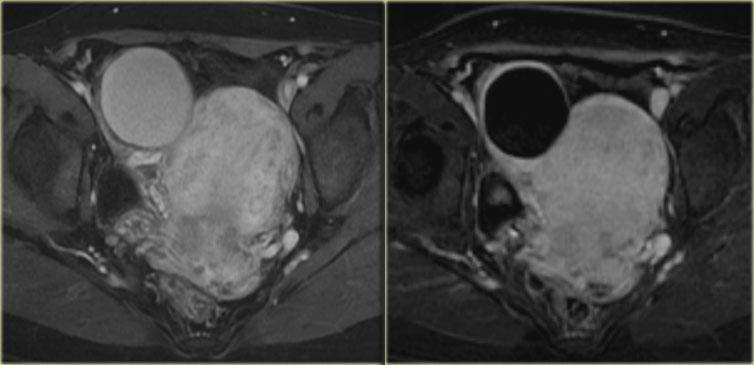

Trên hình ảnh chuỗi xung T1W mặt cắt ngang, cả hai tổn thương đều tăng tín hiệu, gợi ý mỡ, máu hoặc dịch giàu protein.

Kỹ thuật xóa mỡ không làm giảm tín hiệu trong các tổn thương này.

Trong một hình ảnh có kỹ thuật xóa mỡ tổng thể tương đối tốt, điều này loại trừ u quái chứa mỡ và xác nhận gợi ý về dịch xuất huyết.

Trên hình ảnh chuỗi xung T2W mặt cắt ngang, cả hai tổn thương đều cho thấy hình ảnh ‘shading’ điển hình.

Sự sụt giảm dần dần tín hiệu T2 được cho là do sự kết hợp của độ nhớt tăng dần và nồng độ protein cùng sắt tăng dần về phía phần thấp của tổn thương.

Không có ngấm thuốc trên hình ảnh trừ (sau tiêm Gd trừ trước tiêm Gd).

Một lần nữa, kỹ thuật trừ rất hữu ích trong các trường hợp như thế này: sự tăng tín hiệu do Gd gây ra trên nền hình ảnh trước tiêm thuốc vốn đã rất sáng sẽ rất khó nhận biết nếu không có kỹ thuật này.